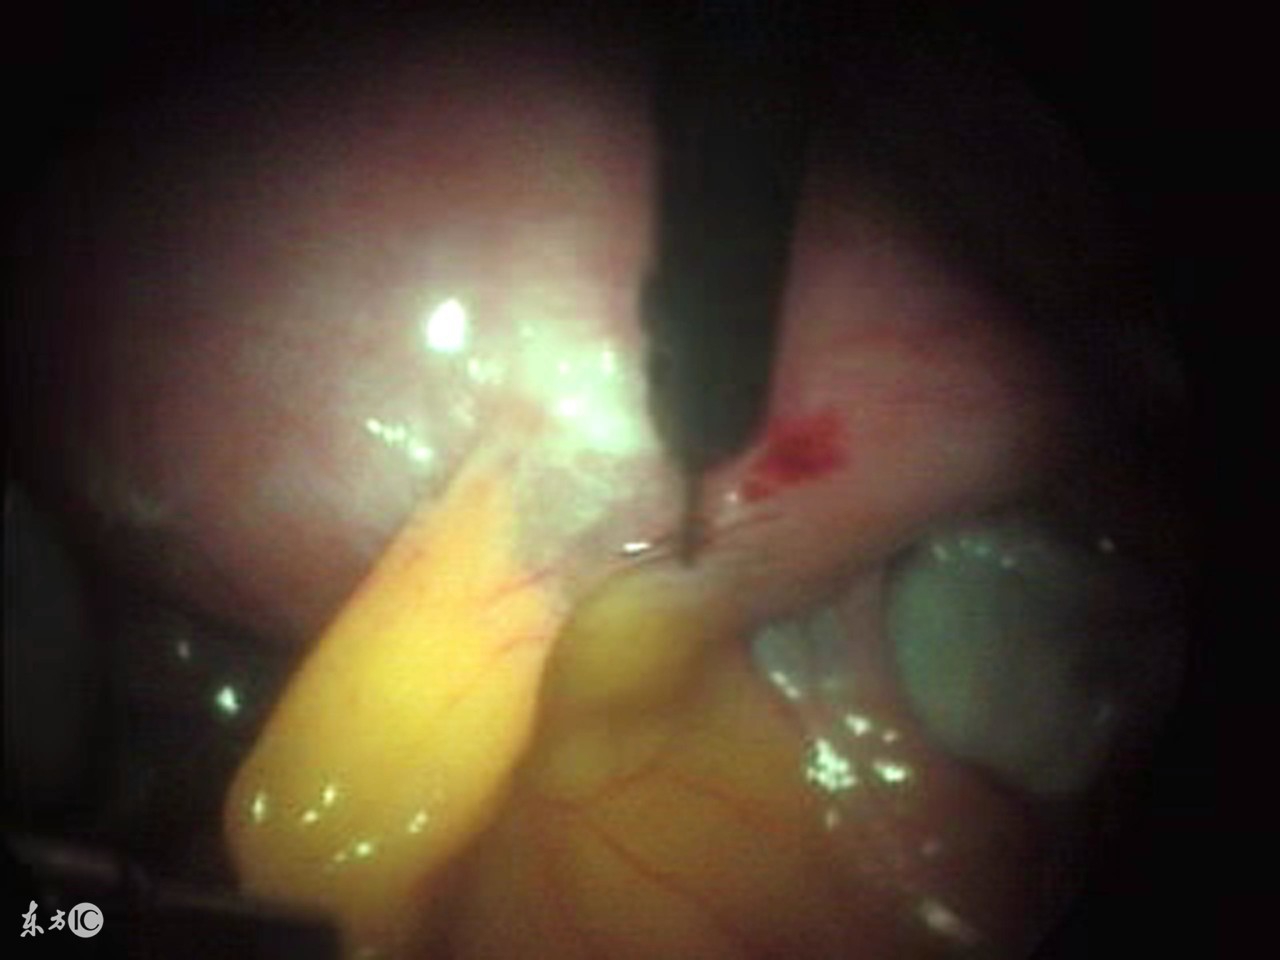

腹腔镜手术作为一种已经广泛运用在临床上的新技术,得到了广大患者的熟知和接受, 腹腔镜手术的原理是利用现代高科技医疗技术用电子、光学等先进设备原理来完成的手术,是传统剖腹手术的跨时代进步,它是在密闭的腹腔内进行的手术:摄像系统在良好的冷光源照明下,通过连接到腹腔内的腹腔镜体,将腹腔内的脏器摄于监视屏幕上,手术医师在高科技显示屏监视、引导下,于腹腔外操纵手术器械,对病变组织进行探查、电凝、止血、组织分离与切开、缝合等操作。

腹腔镜手术是一种微创手术治疗方法,创伤小,恢复快,针对许多疾病的治疗都有很好的作用,比如严重的输卵管阻塞、卵巢囊肿等可以采用腹腔镜手术来治疗,那么做腹腔镜手术需要多少钱呢?